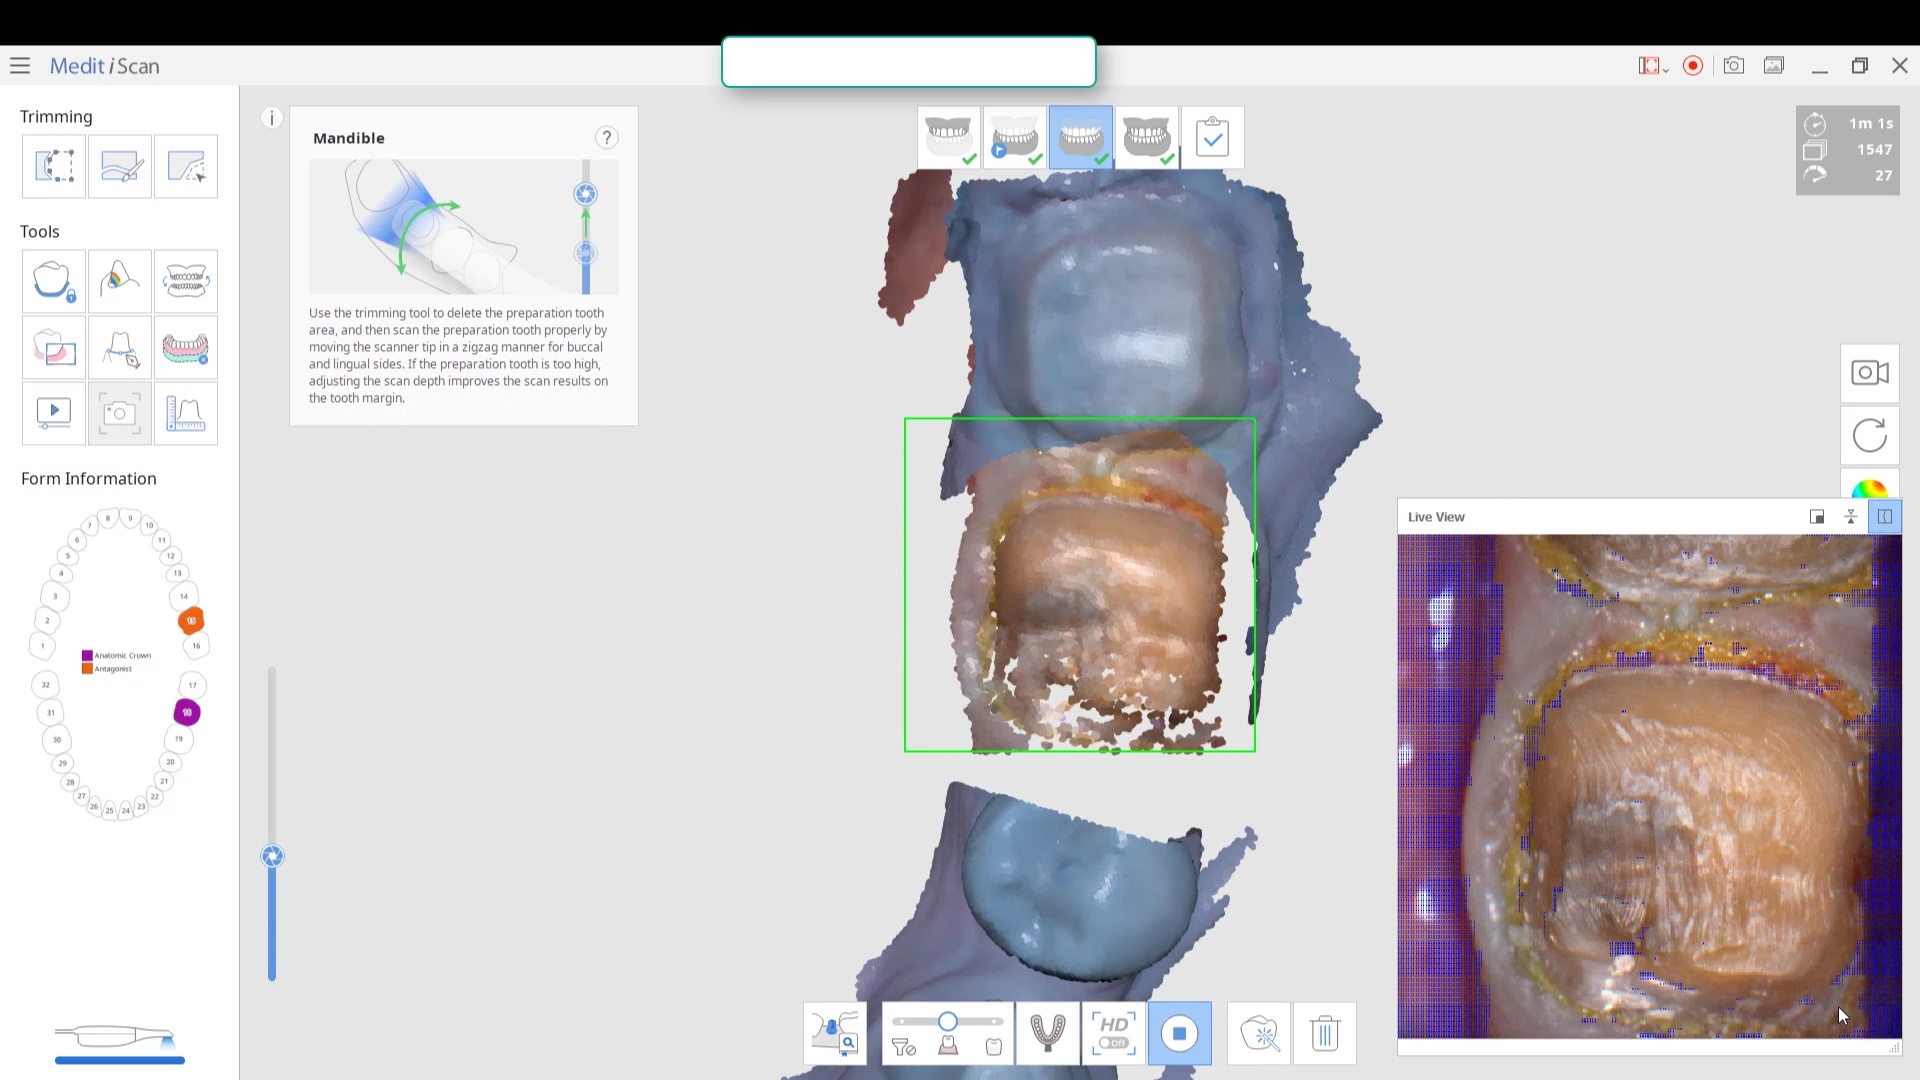

For the second molar, we will take advantage of the anesthesia time and capture the first bite, the opposing, the pre-existing situation and then crop out the preparation area digitally. Once the tooth is prepared, we will check for proper reduction. We will then take the second bite to verify the vertical dimension has not changed.

While the second molar is being designed and milled in the first case, we will launch a second window by cloning the first case. All the data remains the same and this time we crop out the first molar digitally and protect the rest of the arch. Once the first molar is isolated, it is digitally captured and then designed and milled.